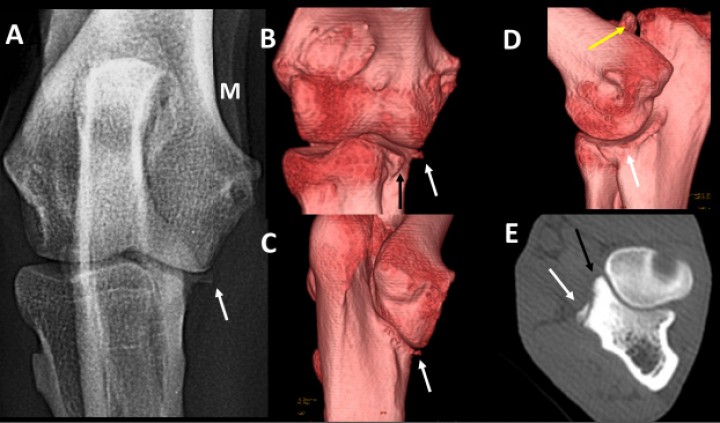

<p>Cruzado macho de 36 meses con dolor en el codo izquierdo. Radiografía craneocaudal (<strong>A</strong>) e imágenes en 3D del codo por las caras craneal (<strong>B</strong>), caudomedial (<strong>C</strong>) y medial (<strong>D</strong>). Plano transversal a la altura de la apófisis coronoides medial (<strong>E</strong>). Se señala la posición de la apófisis coronoides medial (flechas negras) y del osteofito localizado en la porción distal de la escotadura troclear del cúbito (flechas blancas). Es evidente la no unión del proceso ancóneo (flecha amarilla).</p>

Cruzado macho de 36 meses con dolor en el codo izquierdo. Radiografía craneocaudal (A) e imágenes en 3D del codo por las caras craneal (B), caudomedial (C) y medial (D). Plano transversal a la altura de la apófisis coronoides medial (E). Se señala la posición de la apófisis coronoides medial (flechas negras) y del osteofito localizado en la porción distal de la escotadura troclear del cúbito (flechas blancas). Es evidente la no unión del proceso ancóneo (flecha amarilla).

La NUPA se diagnostica fácilmente en una radiografía mediolateral flexionada, por lo que son pocos los casos que nos remiten para diagnosticar la enfermedad mediante TC. Los tres casos remitidos presentaban además EACM y signos de artrosis avanzada. Dada la coexistencia de NUPA y EACM en algunos codos, en nuestra opinión un animal con NUPA debería someterse a una TC para descartar también la presencia de una EACM. De no hacerlo, se podría dar el caso de realizar una cirugía de la enfermedad más llamativa, dejando sin intervenir una EACM que podría haber pasado desapercibida en el estudio radiográfico.